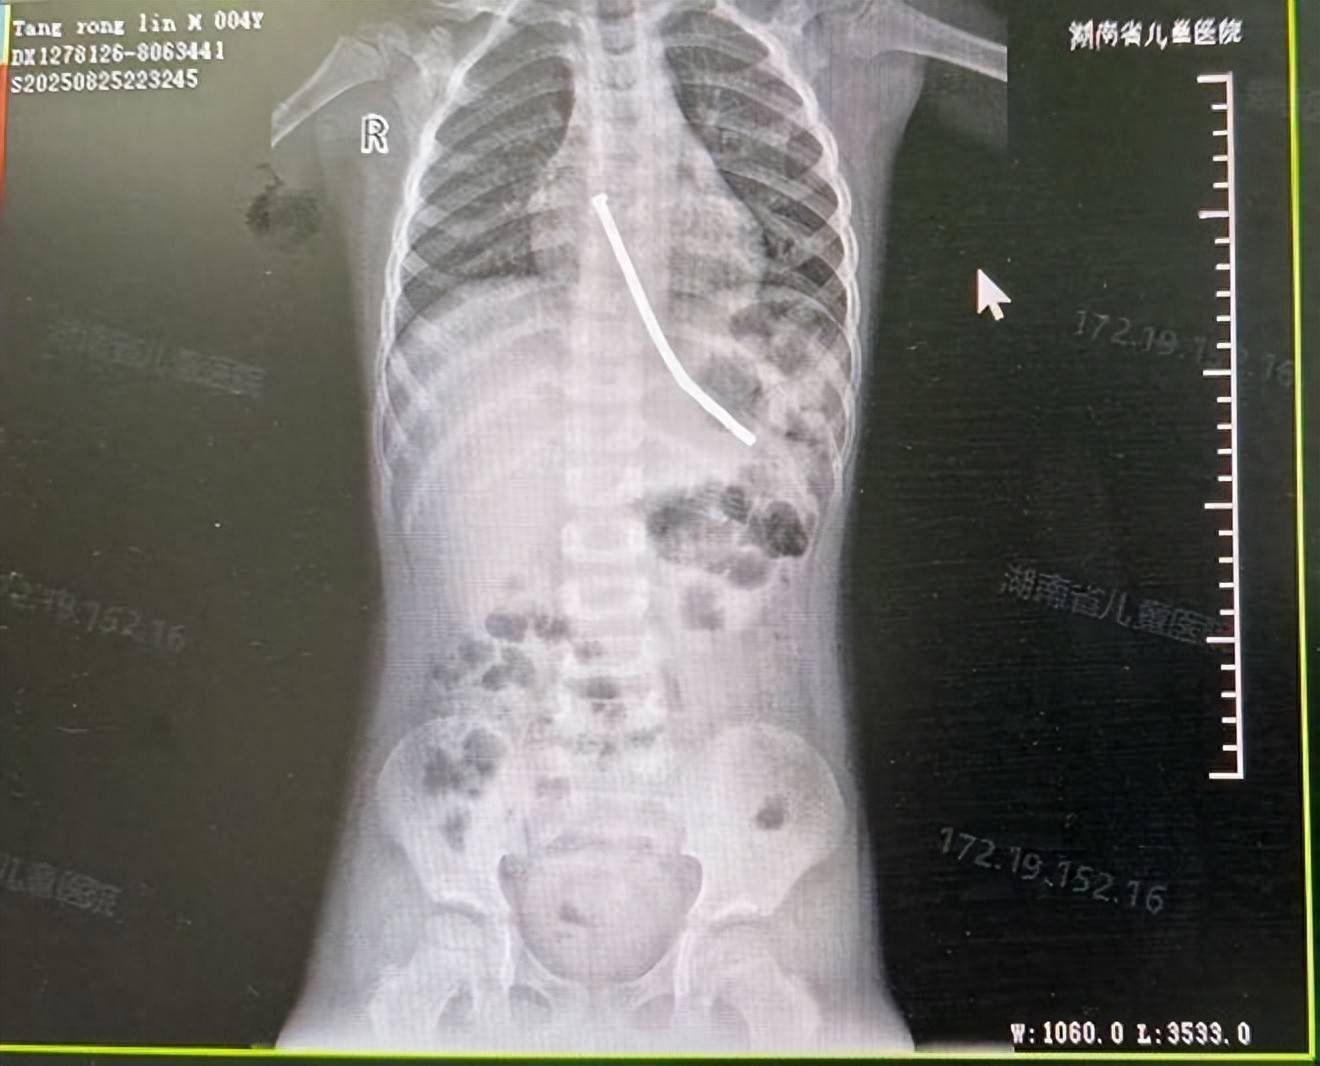

在完善各项术前评估后,医疗团队为东东实施了急诊全麻气管插管下的内镜手术。术中发现,东东的食管和胃内共有40颗磁力珠相互吸附成团,嵌顿于食管壁和胃底部位。由于磁力珠数量多、磁性较强,且滞留时间较长,已造成局部组织严重受压,进而引发缺血和穿孔。

手术内镜团队在精细操作下,成功将全部磁力珠完整取出。随后对穿孔部位情况进行风险评估,并使用了金属肽夹对穿孔部位施行内镜下夹闭术,避免了东东接受外科手术治疗;同时留置了鼻肠管用于后续肠内营养治疗。东东安返病房,生命体征稳定,在消化营养科病房团队的精心护理下,目前东东正在逐步恢复中。